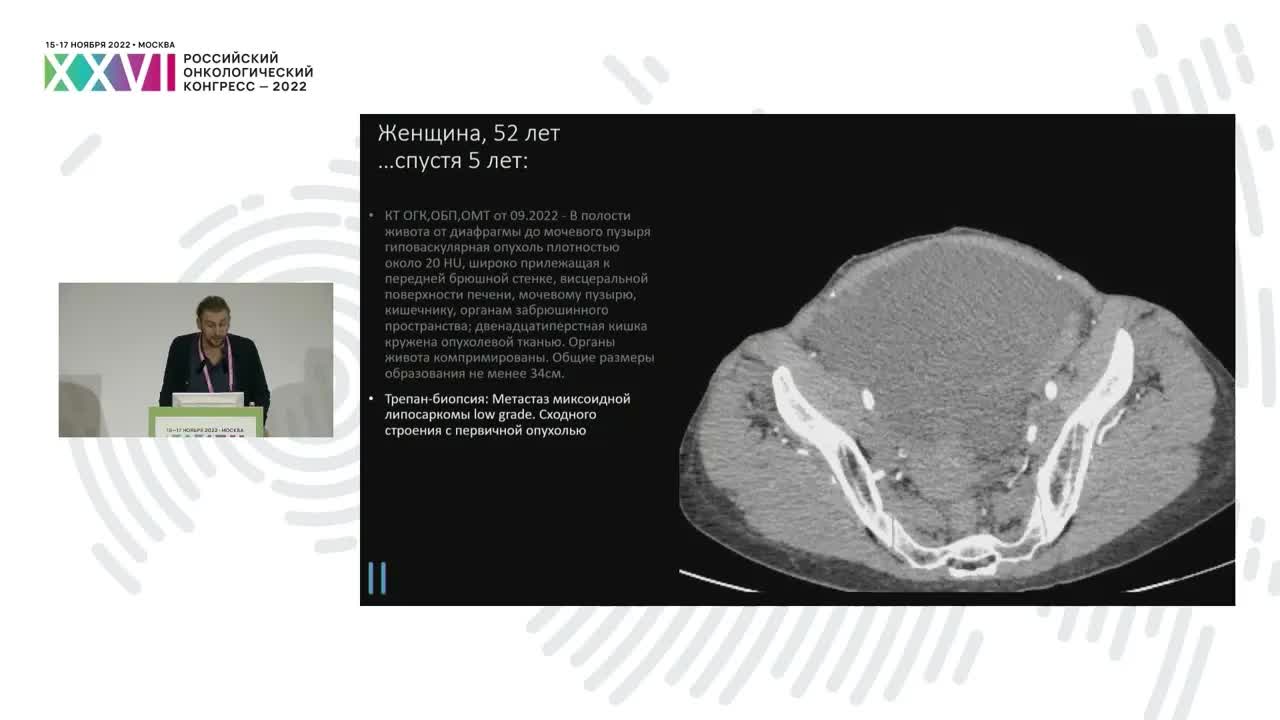

Выбор химиотерапии при лечении саркомы тела матки: доксорубицин против комбинации?

Рябишина Оксана Евгеньевна